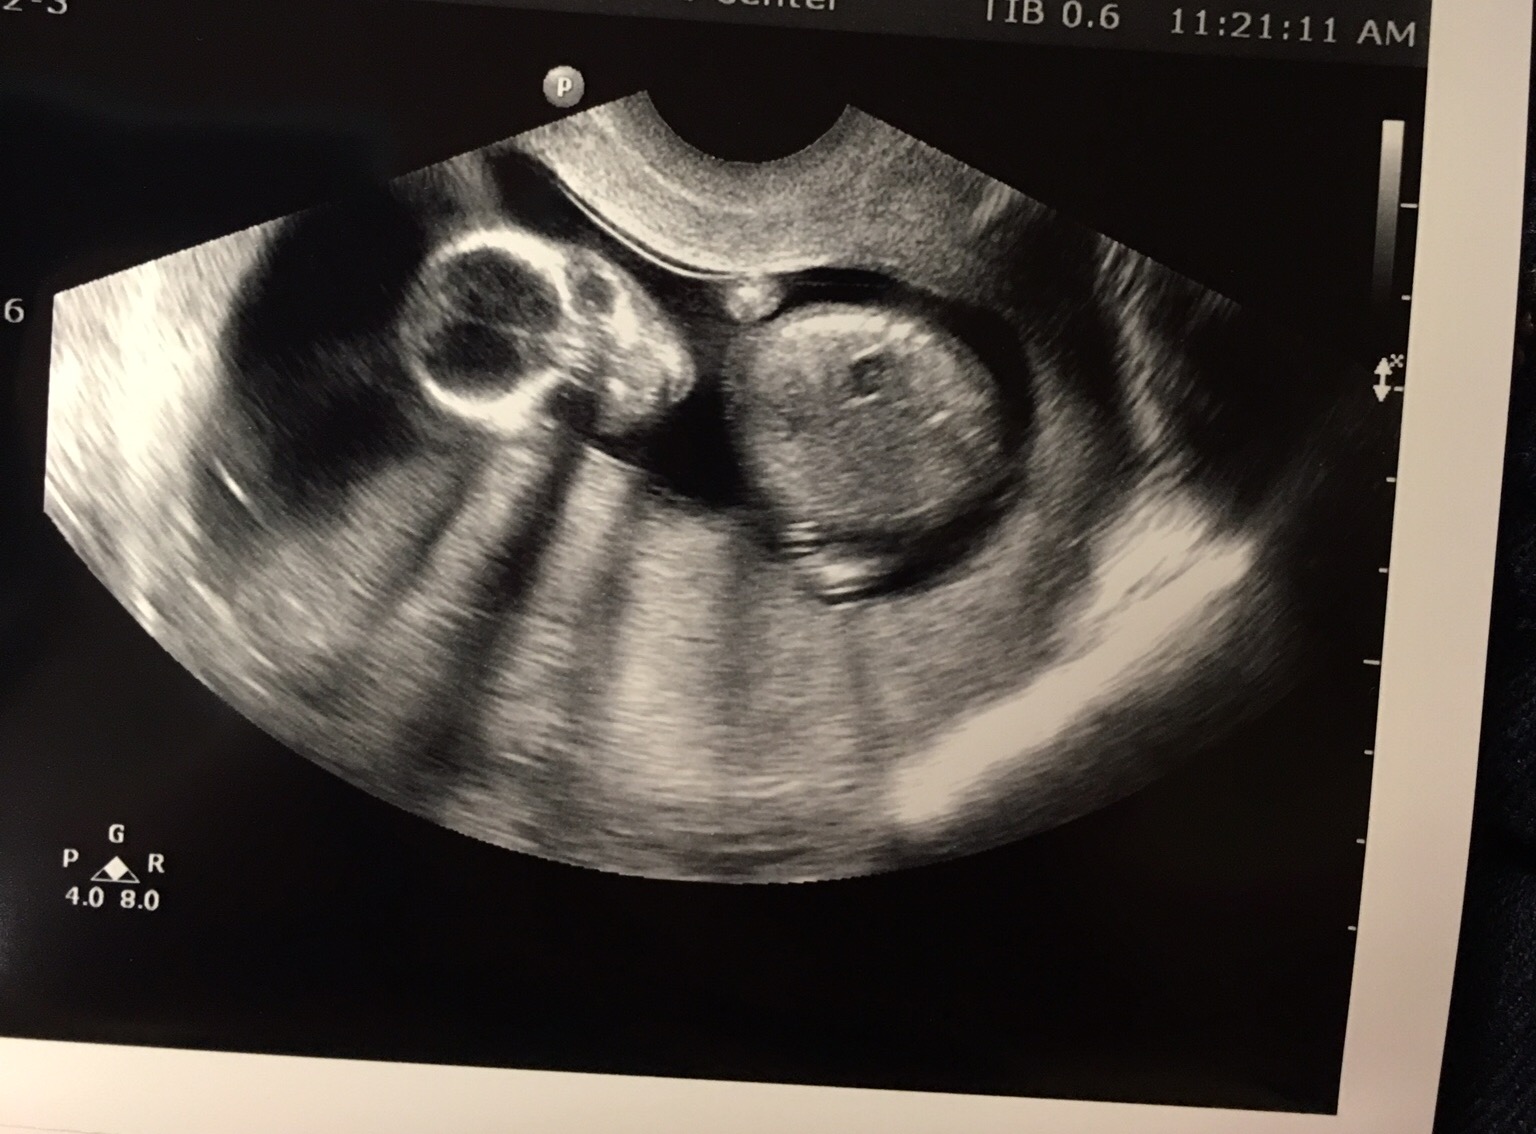

Then the next ultrasound was this past Monday (10 weeks 6 days) and baby was so big! Sleeping at first and then made the meanest face when the tech woke baby up! My husband and I loved it!